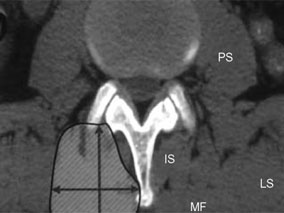

L’étude rétrospective a porté sur 232 patients consécutifs hospitalisés pour TAVI. La surface des muscles psoas a été évaluée par la coupe obtenue au scanner au niveau de la 4e vertèbre lombaire et rapportée ensuite à la surface corporelle totale.

Mesure au scanner de la surface du psoas au niveau de la 4e vertèbre lombaire